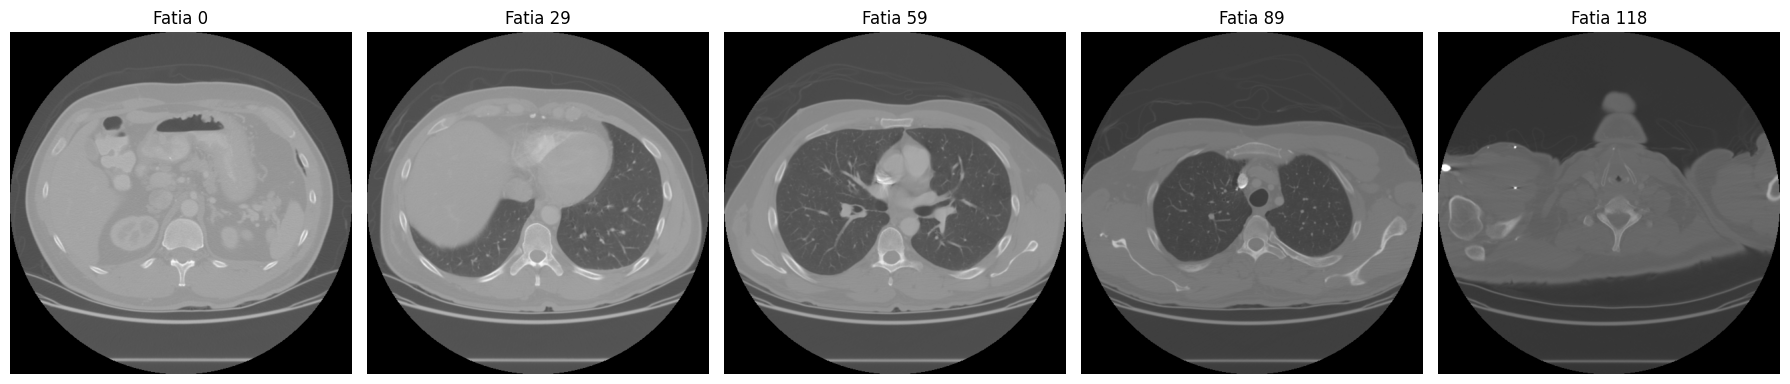

Para ter uma visão geral do volume, podemos exibir fatias espaçadas regularmente:

# exibir 5 fatias distribuidas ao longo do volume

n_fatias = ct_array.shape[0]

indices = [0, n_fatias // 4, n_fatias // 2, 3 * n_fatias // 4, n_fatias - 1]

fig, axes = plt.subplots(1, 5, figsize=(18, 4))

for ax, idx in zip(axes, indices):

ax.imshow(ct_array[idx], cmap="gray")

ax.set_title(f"Fatia {idx}")

ax.axis("off")

plt.tight_layout()

plt.show()

As fatias extremas (0 e 118) mostram pouca anatomia. Conforme avançamos para o centro do volume, pulmões, costelas e coluna vertebral aparecem com clareza.